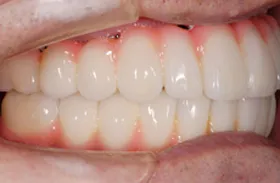

■治療前

■治療後

| 主訴 | しっかりかみたい(咬合障害) |

| 治療方法 | 費用を抑える為、全てインプラントではなく、インプラントを土台とした入れ歯の治療 |

| 治療期間 | 約6か月 |

| 通院回数等 | 約20回 |

| 費用 | 約150万円 |

| リスク・副作用 | 術後の腫れ・痛み |